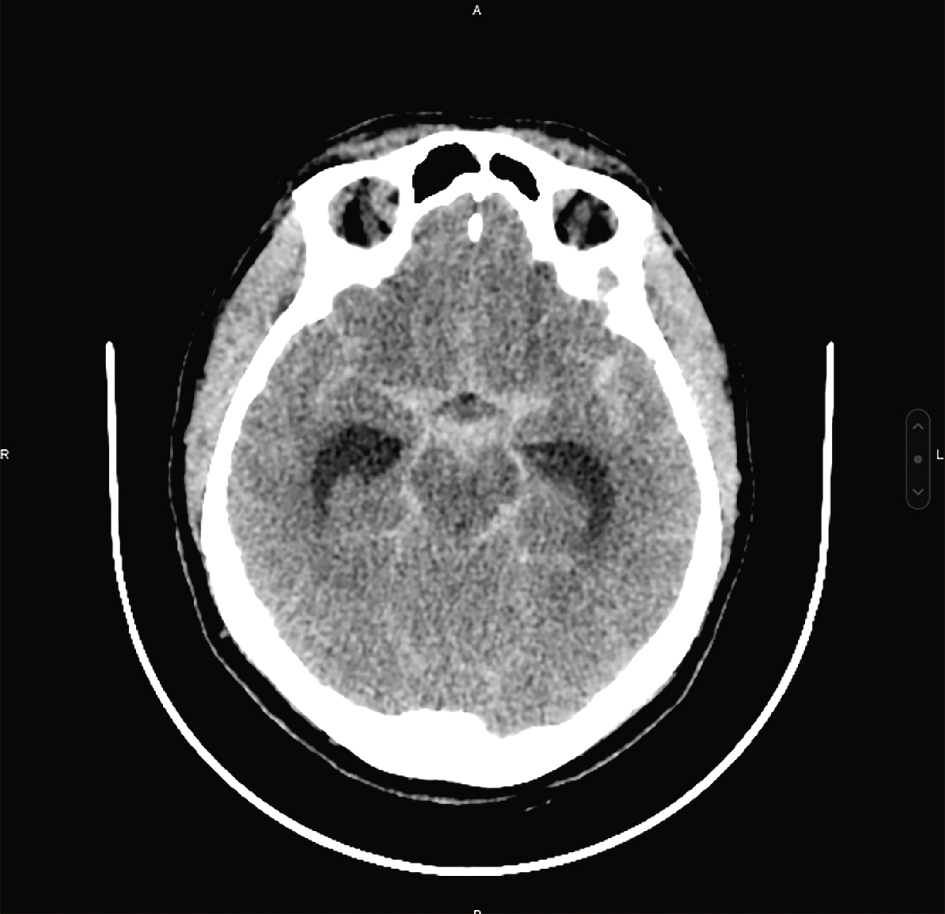

Affirme le diagnostic lorsqu’il montre une hyperdensité spontanée dans les espaces sous-arachnoïdiens : citernes de la base, vallées sylviennes et scissure interhémisphérique essentiellement (fig. 29.1). Les anévrismes étant situés à la base du cerveau, les HSA corticales doivent faire évoquer une étiologie autre qu’anévrismale (syndrome de vasoconstriction cérébrale réversible, thrombose veineuse cérébrale…).

Fig. 29.1

Scanner cérébral sans injection (coupe axiale) montrant une hyperdensité spontanée des citernes de la base, des deux vallées sylviennes.Image de scanner cérébral en coupe axiale, réalisée sans injection de produit de contraste, révélant une hyperdensité spontanée localisée dans les citernes de la base ainsi que dans les deux vallées sylviennes. Cette hyperdensité, visible sous forme de zones blanches au sein des espaces sous-arachnoïdiens, évoque fortement la présence de sang, suggérant une hémorragie méningée aiguë, très probablement d’origine anévrismale. La symétrie des structures cérébrales profondes est globalement respectée, mais la densité accrue dans ces régions clés impose une prise en charge rapide, car elle témoigne d’un saignement actif dans les espaces cérébro-méningés.